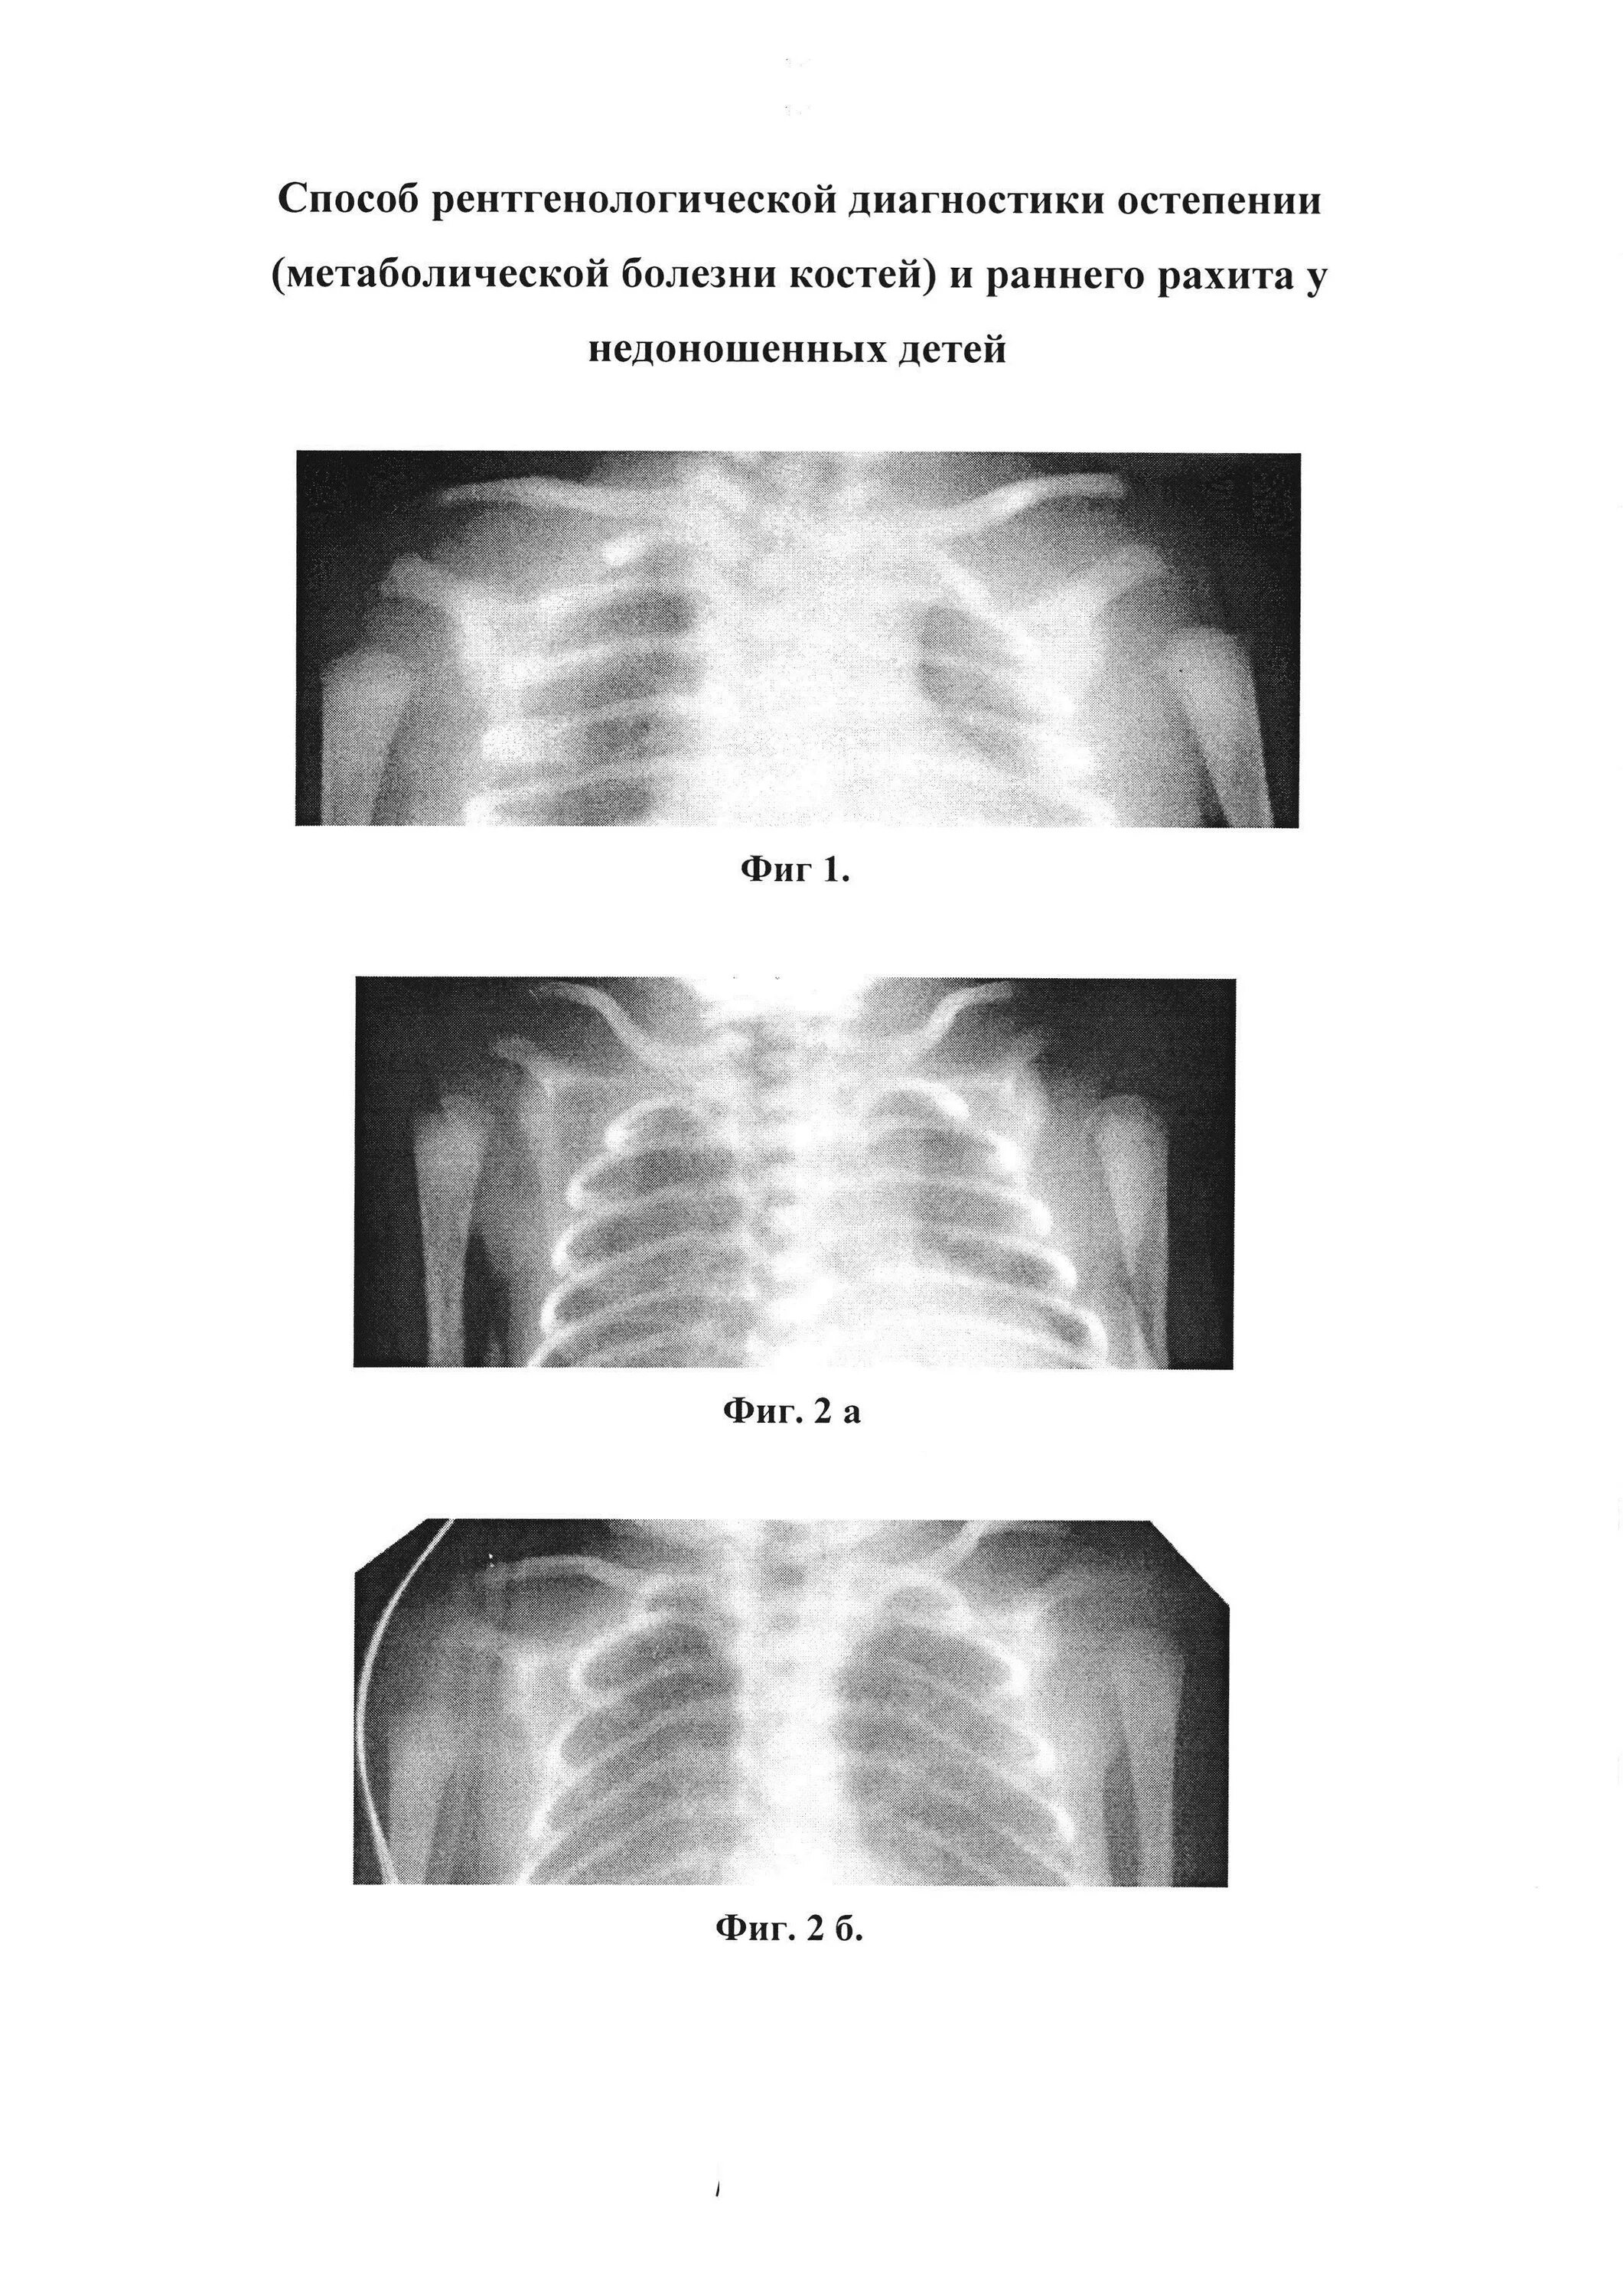

Рахит недоношенных детей